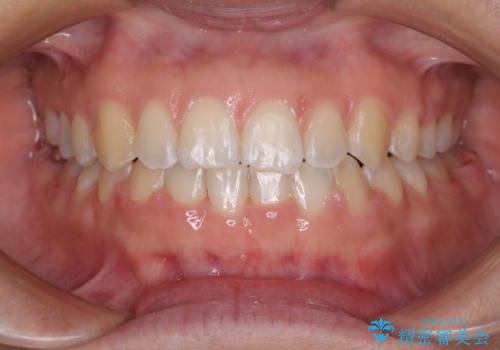

- 下顎前歯が抜けそうとのことで来院された患者様です。

初診の状態ではすぐにでも抜けそうな状態で、インプラントによる補綴治療を行うこととしました。

インプラント治療に際し、前歯の叢生に対する矯正治療を提案したところ、興味を持たれたので、インビザライン・ライトによる矯正治療を行うこととしました。

抜歯後にスペースができると恥ずかしいため、抜歯した歯を接着剤で固定した上で矯正治療を行い、その後インプラントやオールセラミッククラウンの装着を行うこととしました。